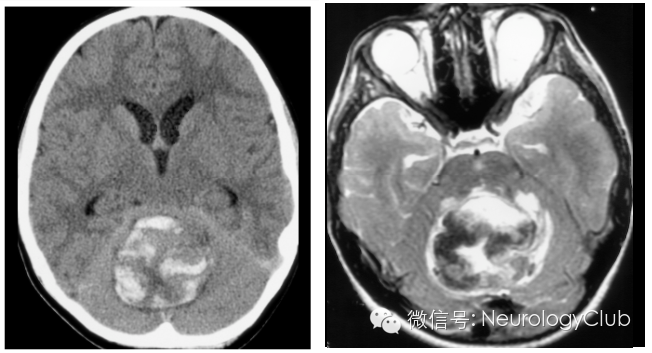

CT显示肿瘤呈边界不清的混杂密度影,常见瘤内出血所致高密度或囊性变、坏死;肿瘤跨胼胝体生长至对侧大脑半球时,呈“蝴蝶征”,水肿和占位效应明显。MRI在一定程度上能够揭示肿瘤的病理改变:T1WI呈不均匀低信号(图 1a),多合并坏死、囊性变或出血性改变;T2WI呈混杂高信号,中心坏死区为高信号,肿瘤生长区周围呈等信号,部分病变与肿瘤周围水肿分界不清,肿瘤内异常血管增生形成线样“流空效应”区(图 1b)。增强扫描肿瘤边缘呈显著对比强化,呈“花环”(ring/rim-enhancing)样(图 1c)、不规则环形、岛形或螺旋形改变;囊变性和坏死区周围肿瘤实质呈特征性“假栅栏征”,即圆形、椭圆形未强化区散在分布在强化区内,类似乳突蜂窝小房。DWI多呈高信号,ADC值明显减低。MRS提示NAA峰降低,Cho升高明显,MI峰较低级别星形细胞瘤低。灌注成像显示,病灶周围和病灶内有多处高灌注区(图 1d),提示大量肿瘤血管生成。胶质母细胞瘤虽具典型影像学特征,但仍需注意与颅内单发转移瘤、间变性胶质瘤、淋巴瘤等肿瘤性病变,以及脑脓肿、结核瘤、脱髓鞘假瘤等非肿瘤性占位性病变相鉴别。

(图2:胶质母细胞瘤)

(图3:蝴蝶征)

(图4:横跨胼胝体的GBM)